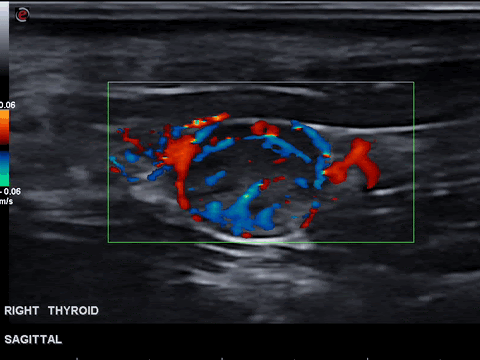

The color doppler appearance of each nodule was graded from 0 for no visible flow through 4 for extensive internal. 2 hyperechoic meaning brighter than normal thyroid fig. Thyroid cancer affects your thyroid gland which is a butterfly-shaped organ in your neck.

Malignant thyroid thyroid cancer ultrasound colors. Colour Doppler image of. Class i prevalence of red and green color.

Several reports have proposed that increased vascular flow on color Doppler sonography may be associated with malignancy in thyroid nodules. The image of both the thyroid nodule and the surrounding thyroid tissue can present as red color affecting a large part of the thyroid gland beyond the nodule under. This paper discusses the role of ultrasound in the management of patients with thyroid cancer.